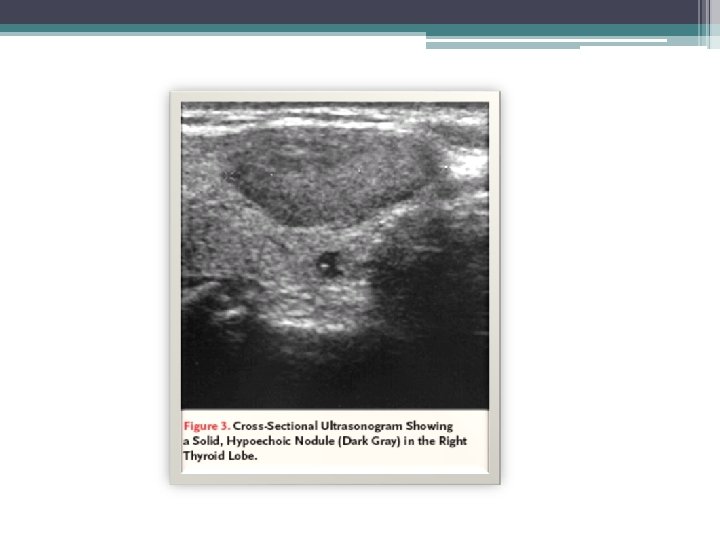

Ultrasound • Provides considerable anatomic information but no functional information • Determine the volume of a nodule, multicentricity and whether it is cystic or solid- often performed before FNA • Extremely useful in also following patients being managed conservatively for possible increasing size of lesion • Unable, however, to accurately predict the diagnosis of solid nodules

Ultrasound • Cystic lesion are reassuring but only 1 -5% of total thyroid nodules • In addition, as many as 25% of well-differentiated thyroid cancers had cystic components and up to 60 -70% of all nodules • Physician correlate the nuclear medicine and U/S finding and determine the function of the particular nodule • Additional nodules can be found 20 -48% of patients • Many times the U/S findings differ from the physical exam, in one retrospective series up to 63% of the time

Ultrasound • Ultrasonographic Cancer Risk Factors for a Thyroid Nodule ▫ ▫ ▫ hypoechogenicity, microcalcifications, irregular margins, increased nodular flow visualized by Doppler, the evidence of invasion or regional lymphadenopathy